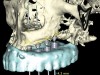

Figure 14  Virtual treatment plan, patient in Figure 12 and Figure 13.

Figure 14